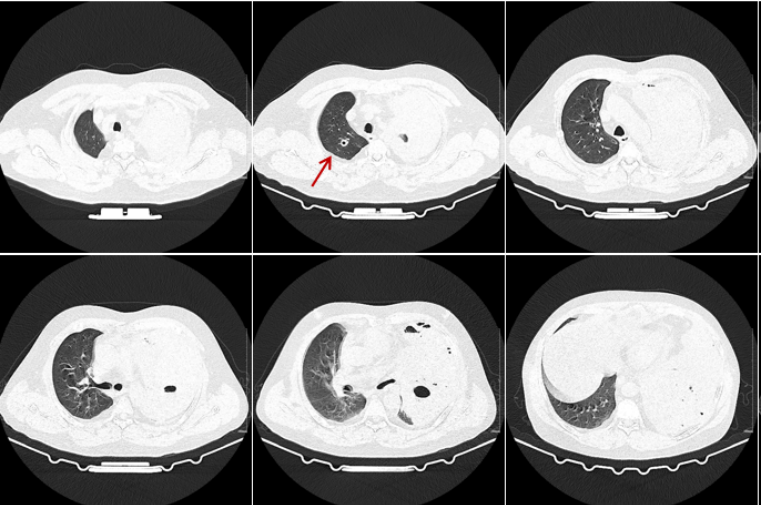

患者咯血,左侧血胸,胸部CT提示左肺团块影,血细胞角蛋白19片段2.84 ng/ml(↑),鳞状上皮细胞癌抗原2.8 ng/ml(↑)。左肺占位性病变,有无肺部肿瘤可能性?回溯患者在我院2023年的胸部CT,未见结节和肿块(图2)。但经过2年时间,病变也可能出现进展。

图片

2  患者2023年1月23日胸部CT